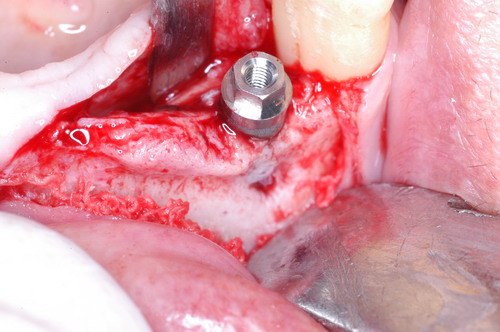

EL USO DEL ARCO GÓTICO DE GYSI , MEDIANTE UNA BÓVEDA PALATINA Y UN APOYO CENTRAL ÚNICO (BO PA YA CU) , EN LA UBICACIÓN DE LA RELACIÓN CÉNTRICA EN UN CASO DE GRAN LAXITUD TENDINOSA CAPSULAR. EL PACIENTE SE PRESENTA A CONSULTA CON UNA EDENTACIÓN PARCIAL, Y GRADO DE MOVILIDAD EXTREMO EN TODAS SUS PIEZAS REMANENTES. SE ESTUDIA EL CASO RADIOGRÁFICA Y CLÍNICAMENTE , Y EL PACIENTE RELATA ESTAR EN ESE ESTADO DESDE HACE MUCHO AÑOS. AL MANIPULAR LA MANDÍBULA EN UN INTENTO DE CONOCER EL ESTADO MUSCULAR DEL SISTEMA, SE OBSERVA UNA GRAN LABILIDAD TENDINOSA CAPSULAR QUE SE MANIFIESTA EN UNA HIPER LAXITUD EN LOS MOVIMIENTOS MANUALMENTE INDUCIDOS DE AMBOS CÓNDILOS DENTRO DE LA CAVIDAD. SE TOMAN IMPRESIONES Y SE MONTA EN UN ARTICULADOR SEMI AJUSTABLE , CORTANDO EN EL YESO LAS PIEZAS QUE SERÁN EXTIRPADAS , CONSERVANDO UNICAMENTE , AMBOS PRIMEROS PREMOLARES INFERIORES , QUE SERÁN UTILIZADOS PARA RETENER MEDIANTE RETENEDORES ELÁSTICOS LA PRÓTESIS INFERIOR , EN LA PRESUNCIÓN DE LA HIPERMOVILIDAD A QUE SERÁ SOMETIDA DADO QUE EN LA GRAN REABSORCIÓN ÓSEA , ES FRECUENTE EL ACERCAMIENTO DE TODAS LAS INSERCIONES MUSCULARES A LA PORCIÓN SUPERIOR DEL REBORDE ÓSEO , LO QUE ATENTARÁ CONTRA LA ESTABILIDAD DE DICHA PRÓTESIS PROVISIONAL. EN UNA PRIMERA SESIÓN CLÍNICO QUIRÚRGICA , SE EXODONCIA TODO EL SECTOR INCISIVO Y CANINO INFERIOR , Y AL OBSERVAR EL REMANENTE ÓSEO CANINO DE AMBOS LADOS , SE IMPLANTA EN FORMA INMEDIATA . TANSCURRIDOS DOS MESES , DONDE LA CICATRIZACIÓN ES ADECUADA , Y LA DINÁMICA MANDIBULAR ACEPTABLE , SE PROCEDE A LA ETAPA QUIRÚRGICA IMPLANTARIA MEDIANTE IMPLANTES SEMI SUMERGIDOS, CON ALGUNAS ZONAS DE REGENERCIÓN ÓSEA GUIADA FIG17 FIG18 FIG19 FIG26 DURANTE LA ETAPA DE CICATRIZACIÓN DE ESTE NUEVO ABORDAJE QUIRÚRGICO , SE ENDODONCIAN AMBOS PREMOLARES INFERIORES CONSERVADOS , LOS QUE EN UN FUTURO , CUANDO YA NO SIRVAN PARA RETENER LA PRÓTESIS REMOVIBLE PROVISORIA INFERIOR , SERÁN CORTADOS COMO RESERVA DE CAPITAL ÓSEO O BIEN COMO ELEMENTO RETENEDOR ANTE CUALQUIER TIPO DE INCIDENCIA IMPLANTARIA. ABORDAMOS LA ETAPA PRIMARIA PROTÉTICA , UNA VEZ TRANSCURRIDOS TRES MESES, MEDIANTE LA UTILIZACIÓN DE CUBETAS INDIVIDUALES , A LAS QUE REALIZAMOS UN RECORTE MUSCULAR EN BASE A STENS VERDE , COMO SI DE UNA PRÓTESIS COMPLETA SE TRATARA. DE ESE MONTAJE OBTENEMOS DOS RODETES DE METACRILATO , PERFECTAMENTE ADAPTADOS A LOS MODELOS FUNCIONALES , A LOS QUE LES OTORGAMOS LA PLANIMETRÍA DERIVADA DEL PARALELISMO CON EL PLANO DE FRANKFURT , Y UNA ALTURA (DV) QUE RESULTA DE LOS MÉTODOS MÉTRICOS DE DIMENSIÓN VERTICAL… Y QUE NOS SERVIRAN ADEMÁS DE TOMAR UNA NUEVA IMPRESIÓN FUNCIONAL MEDIANTE RECORTE MUSCULAR , PARA ADAPTAR UN DISPOSITIVO CONSISENTE EN UNA BÓVEDA PALATINA SUPERIOR , Y UN TORNILLO CENTRAL INFERIOR , LOS QUE DESPUÉS DE UN ENTRENAMIENTO ADECUADO DEL ENFERMO , NOS PERMITIRÁ REPRODUCIR EN EL BÓVEDA , EL ARCO GÓTICO DE GYSI , ENCONTRANDO DE ESTA MANERA LA OCLUSIÓN EN RELACIÓN CÉNTRICA. ACTUALMENTE ESTE MÉTODO HA SIDO RECREADO MEDIANTE LA DENOMINACIÓN DE: FIG50 FIG51 FIG52 OBTENIDO EL DIBUJO DEL ARCO GÓTICO , INSINUAMOS EN EL VÉRTICE DEL MISMO UNA PERFORACIÓN QUE FIJARÁ LA PUNTA DEL TORNILLO EN ESA POSICIÓN: RELACIÓN CÉNTICA FIG55 FIG56 FIG57 CON ESTOS PARÁMETROS SE CONSTRUYEN DOS SOBREDENTADURAS ABROCHADAS EN RÓTULAS SUPRA IMPLANTES , QUE LE OTORGAN FIJACIÓN SUFICIENTE , DANDO A LA OCLUSIÓN TODOS LOS ELEMENTOS DE UNA: OCLUSIÓN MUTUAMENTE COMPARTIDA, REFERENCIA II CON UN ESQUEMA OCLUSAL DE : FUNCIÓN DE GRUPO BILATERAL POSTERIOR DE ACCIÓN CANINA DESPUÉS DE LAS REVISIONES PERTINENTES A LA SEMANA , EL MES Y LOS SEIS MESES DE TERMINADA LA REHABILITACIÓN , SE CITA AL ENFERMO PARA UN NUEVO CONTROL AL AÑO Y MEDIO Y SE OBSERVA UNA PERFECTA SITUACIÓN TISULAR , CLINICA Y RADIOGRAFICAMENTE CONTROLADA , Y ADEMÁS LA PERMANENCIA DEL MISMO ESQUEMA OCLUSAL OTORGADO DESDE EL PRINCIPIO. SE CONTROLA RADIOGRAFICAMENTE Y SE DA EL ALTA DEFINITIVA RECOMENDANDO EL CONTROL DOS VECES AL AÑO. REFERENCIAS: I : II. : III: